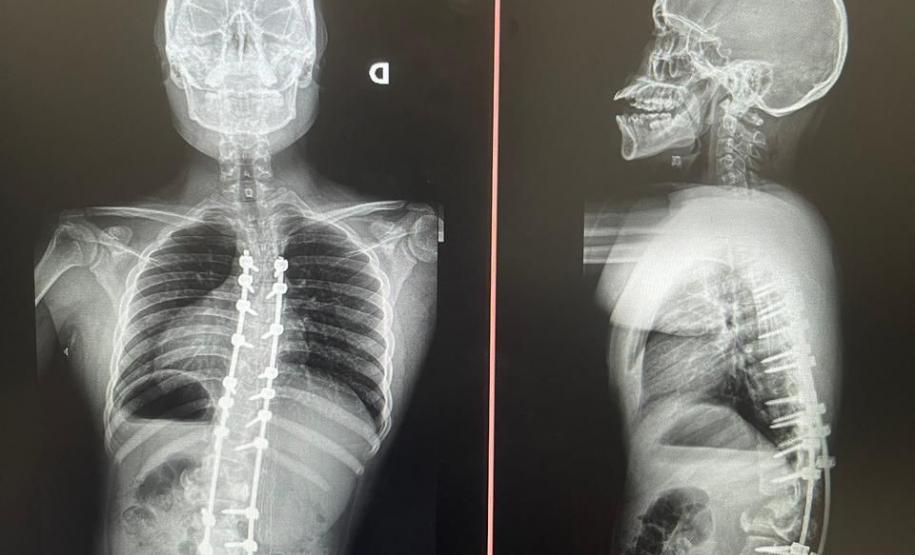

Além do tratamento por meio do uso de coletes ortopédicos, gesso e fisioterapia, em alguns casos é necessária a cirurgia para correção do desvio. A Sesa implantou no Complexo Hospitalar do Trabalhador (CHT) o Serviço de Deformidades Pediátricas da Coluna Vertebral e, em pouco mais de um ano, já realizou pelo Sistema Único de Saúde (SUS) mais de 50 cirurgias de escoliose em crianças e adolescentes entre 3 e 18 anos. Outras 47 já estão agendadas para serem feitas tanto no Hospital de Reabilitação (HR) quanto no Hospital do Trabalhador (HT).

Aos 14 anos, a adolescente Milena de Andrade Carvalho, moradora de Guaratuba, no Litoral do Estado, foi diagnosticada com escoliose idiopática. Sem causa definida, esse tipo de escoliose pode surgir a partir dos quatro anos até a adolescência e ocorre durante o estirão de crescimento. Quando a condição da curvatura ultrapassa os 40 graus, a escoliose se torna progressiva e o paciente continua entortando. Essa condição ocorre com maior frequência em meninas e é muito importante que os pais estejam atentos a qualquer sinal do problema.

“Descobrimos a escoliose por acaso, nunca tínhamos percebido a deformidade, até que um dia ao amarrar meu biquíni, minha mãe observou que eu estava com a coluna torta e ao passar a mão percebeu a curvatura. Decidimos então procurar atendimento médico e tive o diagnóstico da doença já com 50 graus de curvatura e indicação imediata de cirurgia”, contou a adolescente.